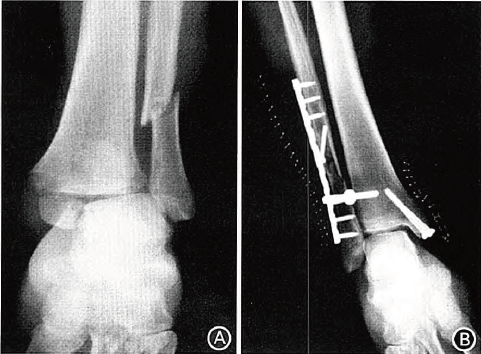

图1 Denis—weber C型踝关节骨折合并下胫腓联合分离,使用下胫腓钩固定。A.术前x线片示下胫腓联合分离 B.术后x线片示下胫腓复位